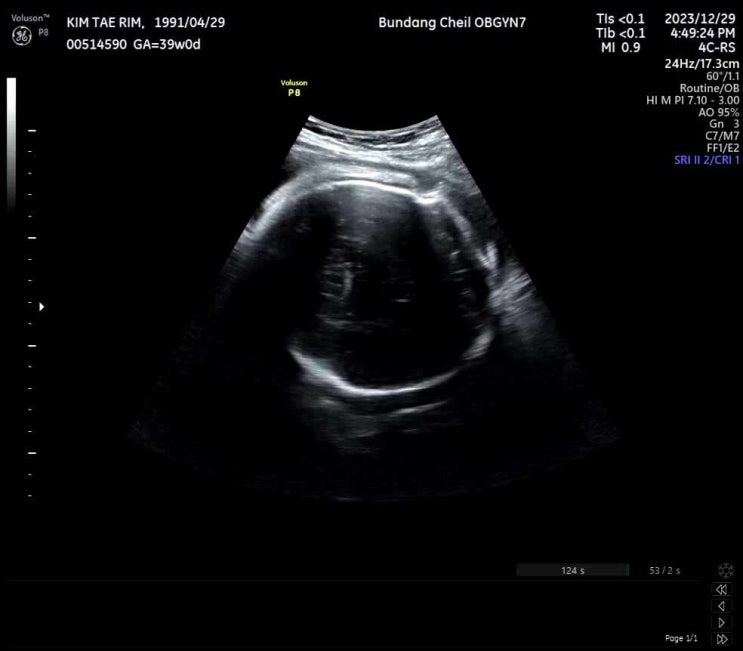

[39주](23.12.29.) D-7

임신확인서에는 1월 6일로 써있었는데 예정일이 5일이었음;; ㅋㅋㅋㅋㅋㅋ 5일이나 6일이나.. 난 단비가 4...